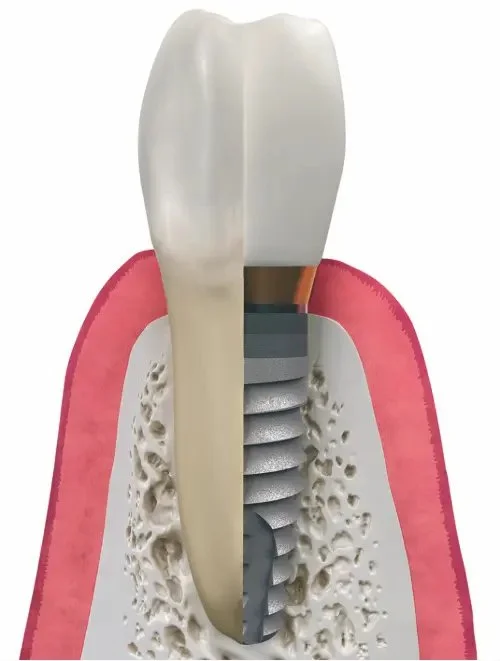

The implant acts as the “root” of your new tooth.

After placement, the implant undergoes a natural healing process called osseointegration. This means the bone fuses to the implant surface, creating unmatched stability.